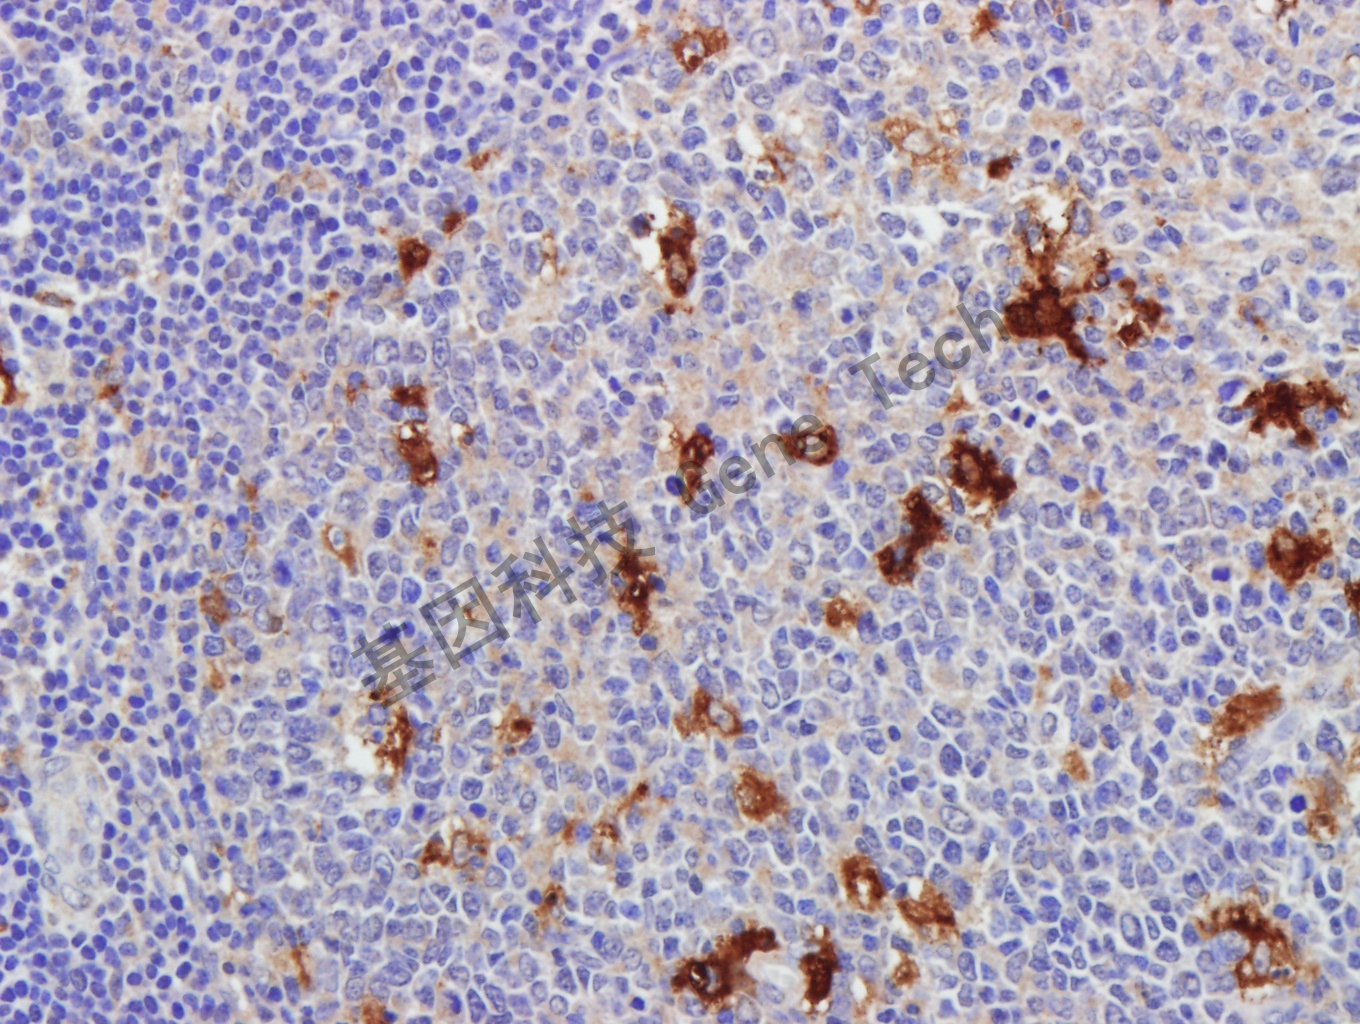

Lysozyme 兔抗人 Lysozyme 抗體試劑(免疫組織化學(xué))

| 預(yù)處理:高pH熱修復(fù) | 陽性部位:細(xì)胞漿 | 陽性對照:扁桃體 |

| 扁桃體石蠟切片,用 Lysozyme(GA0099)染色,細(xì)胞漿陽性,DAB 顯色。 | ||